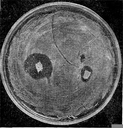

Рис. 2. Приклад антагонізму в мікробів. Видна зона придушення росту стафілококу навколо агарового блоку з культурою актиноміцету.